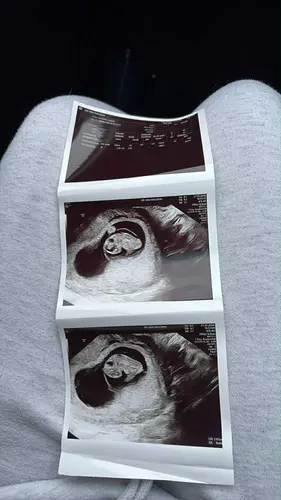

Eerste echo nu 8 weken en 5 dagen